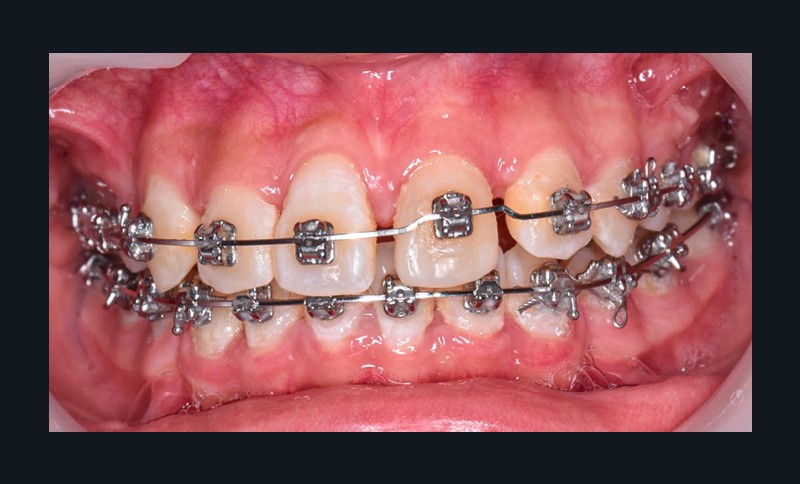

L’objectif du traitement est la correction de la DDA tout en assurant le remplacement de la 21 compromise. Décision a été prise d’extraire 34 et 44, ainsi que 21 et 14. La traction de la 23 a été réalisée à l’aide de forces légères, sur un arc transpalatin (fig. 9). Le nivellement et l’alignement, puis une mécanique par glissement ont permis d’aménager l’espace suffisant à la stratification de la canine. Elle associait un ressort en nickel-titane à des élastiques de Classe II (4 ½ oz, 3/16’’) sur un arc en acier .019×.025. Une phase d’ingression a été réalisée pour ajuster le niveau du bord libre de la canine à celui de l’incisive controlatérale (fig. 10-12).